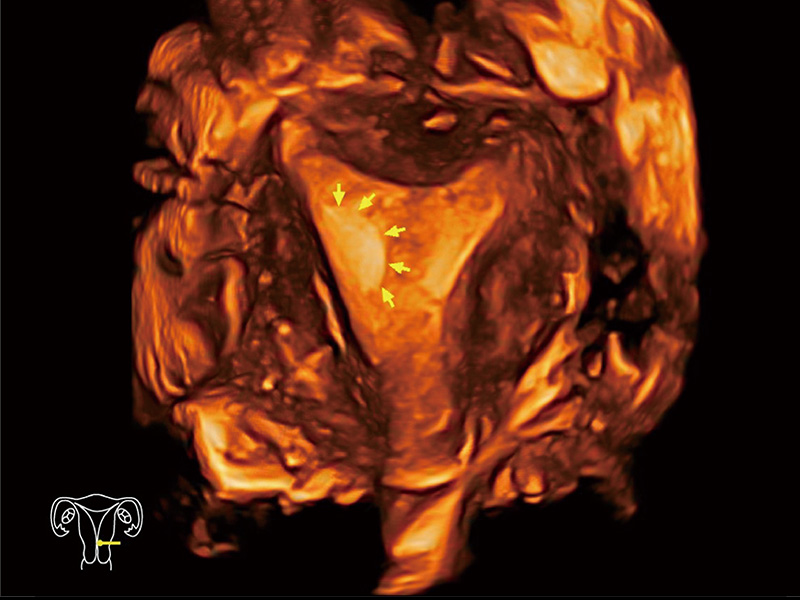

临床图

中央型宫腔粘连

腔内三维成像技术获得显著提升,超大扇角在满足日常基础扫查的同时,支持卵泡自动测量及多种三维渲染模式,为您提供更多的诊断信息,尤其是在子宫畸形的诊断,内膜及肿瘤占位观测中起到了重要的作用。